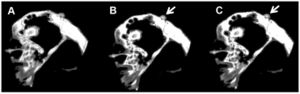

Diffusion Tensor Imaging Assessment of Microstructural Brainstem Integrity in Chiari Malformation Type I.

Publication: J Neurosurg. 2016 Feb 5:1-8. PMID: 26848913 Authors: Krishna V, Sammartino F, Yee P, Mikulis D, Walker M, Elias G, Hodaie M. Institution: Department of Neurosurgery, Ohio State University, Columbus, Ohio. Background/Purpose: OBJECTIVE The diagnosis of Chiari malformation Type I (CM-I) is primarily based on the degree of cerebellar tonsillar herniation even though it does not always correlate with symptoms. Neurological dysfunction in CM-I presumably results from brainstem compression. With the premise that conventional MRI does not reveal brain microstructural changes, this study examined both structural and microstructural neuroimaging metrics to distinguish patients with CM-I from age- and sex-matched healthy control subjects. METHODS Eight patients with CM-I and 16 controls were analyzed. Image postprocessing involved coregistration of anatomical T1-weighted with diffusion tensor images using 3D Slicer software. The structural parameters included volumes of the posterior fossa, fourth ventricle, and tentorial angle. Fractional anisotropy (FA) was calculated separately in the anterior and posterior compartments of the lower brainstem. RESULTS The mean age of patients in the CM-I cohort was 42.6 ± 10.4 years with mean tonsillar herniation of 12 mm (SD 0.7 mm). There were no significant differences in the posterior fossa volume (p = 0.06) or fourth ventricular volume between the 2 groups (p = 0.11). However, the FA in the anterior brainstem compartment was significantly higher in patients with CM-I preoperatively (p = 0.001). The FA values normalized after Chiari decompression except for persistently elevated FA in the posterior brainstem compartment in patients with CM-I and syrinx. CONCLUSIONS In this case-control study, microstructural alterations appear to be reliably associated with the diagnosis of CM-I, with a significantly elevated FA in the lower brainstem in patients with CM-I compared with controls. More importantly, the FA values normalized after decompressive surgery. These findings should be validated in future studies to determine the significance of diffusion tensor imaging-based assessment of brainstem microstructural integrity as an adjunct to the clinical assessment in patients with CM-I. |